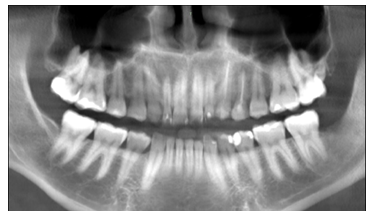

Posterior a 3 meses, se realizó un nuevo estudio radiográfico en el cual se demostrando el tratamiento finalizado, sin secuelas aparentes de una posible recidiva del queratoquiste odontogénica, visualizando la recuperación total de la U.D 37. Se le indicó Tratamiento endodóntico en la U.D 37.